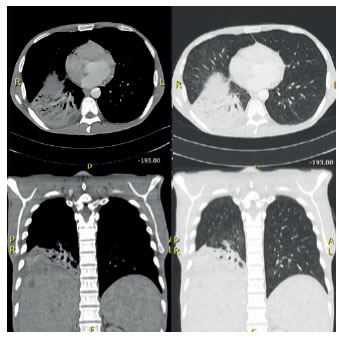

En los exámenes paraclínicos de control se encontró: albúmina, 2,5 g/dl; fosfatasa alcalina, 1.094 U/L; bilirrubina total, 5,5 mg/dl y directa de 4,3 mg/dl, y los marcadores tumorales (alfa-fetoproteína, Ca19,9 y antígeno carcinoembrionario) fueron negativos. En la tomografía computarizada (TC) de tórax se observó un extenso compromiso parenquimatoso pulmonar en el lóbulo inferior derecho, tabiques en la pleura parietal hacia el aspecto medial del lóbulo inferior derecho y una zona que podría corresponder a una neumonía necrosante (figura 1). Se hospitalizó para estudio y tratamiento.